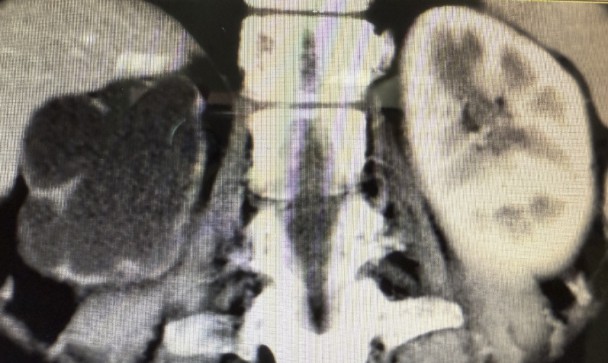

近日,我院泌尿外科团队成功为一位饱受多年右侧腰腹部疼痛困扰的67岁患者(化名:李阿姨),实施了高难度、高精度的腹腔镜下右肾切除术。手术过程顺利,患者恢复良好,术后第4天即康复出院。 李阿姨长期遭受右侧腰腹部的疼痛困扰。来院就诊后,泌尿外科蒋勇军主任详细询问病史得知,她曾因右侧肾结石接受过手术治疗。进一步的系统检查(包括下腹部CT平扫和CT尿路成像)揭示了问题根源:患者右侧肾脏存在严重肾积水,肾实质已极度萎缩、变薄,功能完全丧失。影像学显示,在排泄期长时间观察下,右肾已无显影,确认其功能完全丧失。 蒋主任分析认为,患者既往的结石病史可能导致输尿管狭窄或闭锁,引发了长期的尿路梗阻和肾积水,最终造成右肾不可逆的萎缩。而萎缩肾脏可能存在的炎症,正是其持续疼痛的原因。 面对患者切除无功能病肾的诉求,蒋勇军主任团队经过严谨评估,决定迎难而上,采用腹腔镜微创技术实施右肾切除术。该手术属于最高难度的四级手术,对医院综合实力和主刀医生的技术要求极高。手术面临两大挑战: 1、组织粘连重:萎缩的肾脏因继发炎症,与周围组织形成致密粘连,分离难度大。 2、血管处理难:萎缩肾脏的血管结构不清、纤细且被纤维组织包裹,解剖分离需极其精准,稍有不慎易损伤邻近重要血管和器官。 6月17日,手术如期进行。术中腹腔镜视野下,可见患者右肾萎缩呈“皮囊样”,肾实质薄如纸片,与周围组织粘连紧密,肾血管结构不清。蒋勇军主任团队凭借丰富的腹腔镜操作经验和精湛的解剖技巧,如同精雕细琢般,仔细分离粘连组织,精准处理纤细的肾血管及输尿管,最终完整、安全地切除了病变右肾。手术历时约3小时,顺利完成。 术后病理检查结果证实为“肾萎缩”,与术前诊断完全一致。在泌尿外科医护团队的精心治疗和护理下,李阿姨恢复迅速,疼痛解除,术后第4天即满意出院。出院前,蒋主任特别叮嘱她:务必保护好唯一的左肾,定期复查泌尿系统,发现异常及时就医处理。